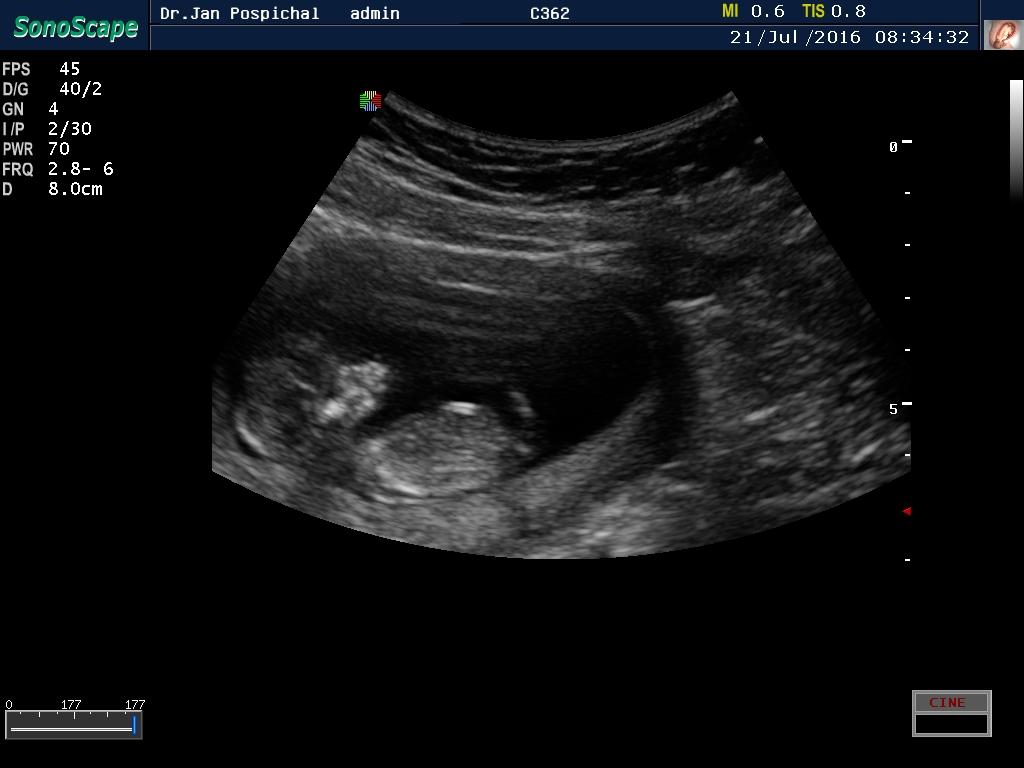

Je to holčička nebo chlapeček? Foto ultrazvuku

Ahoj maminky a budoucí maminky 😉 Prosím, poradila byste mi některá, co vidíte na fotce z ultrazvuku ve 20. týdnu za pohlaví? Určitě jste foteček viděly už mraky, proto vás žádám o radu...Nechci nikoho ovlivnit, proto svůj tip řeknu později 🙂 Děkuju moc!!!

@mariejosef holky já od 13 tt věděla, že mám holku. zrovna byl u doktorky student a bylo vysvětleno, že pokud je ten vyrusze vodorovně s páteří, je to holka a pokud je vychyleny, je to kluk

@mariejosef takže bych řekla asi holka 😉

@ellilenka řekla bych že malá princezna

@ellilenka jasna holcicka

@irisv podle té teorie co řekli loni mně, tak holka, takto jsme to měli ve 13 tt také....vodorovné s páteří

@mariejosef: A to je pindík jo ? Tý brďo já bych to podle toho směru spíš tipla na holku :D ale nejsem doktor :/